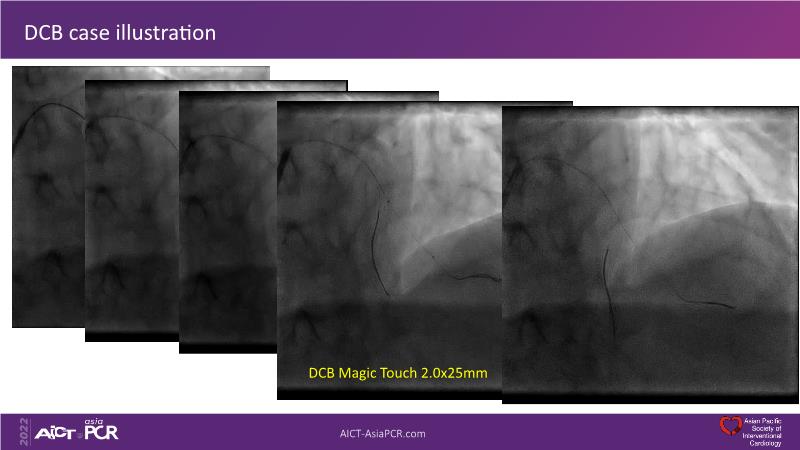

Consult this session to understand the technology and scientific evidence of the novel sirolimus drug-coated balloon, to learn its utility for PCI in a variety of lesion and patient subsets and to understand the evidence and outcomes in real-world patients.

- To understand the technology and scientific evidence of the novel sirolimus drug-coated balloon (SDCB)

- To learn the utility of the DCB for PCI in a variety of lesion and patient subsets